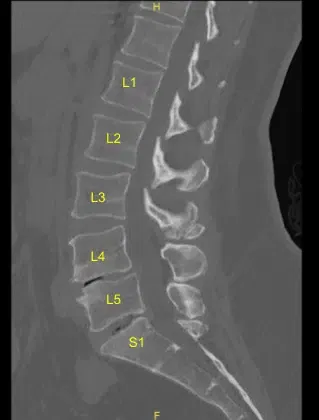

The imaging showed malfunction and suboptimal placement of the right sacral pedicle screw. Surgery was recommended to decompress the lumbar nerve root being impinged by the pedicle screw and stabilize the lumbar spine.

Intraoperative CT scan was obtained, and data was transferred to the neuronavigation computer and accuracy was verified. Neuronavigation techniques were used to cannulate the right-sided first sacral segment which was then palpated for breaches and measured at the depth of 35 mm. A 6.0 mm navigated tap was used to thread the cannulation. It was again palpated for breaches and a 7.5 x 35 mm titanium pedicle screw was placed with good bony purchase and tightness.

Next, the patient was re draped and a second intraoperative CT scan was obtained showing correct positioning of this pedicle screw. Neuromonitoring signals were stable throughout. Next, the L5-S1 transverse process and ala were decorticated with a high-speed drill for the arthrodesis after exploring the fusion and failing to identify bony arthrodesis and bone graft.